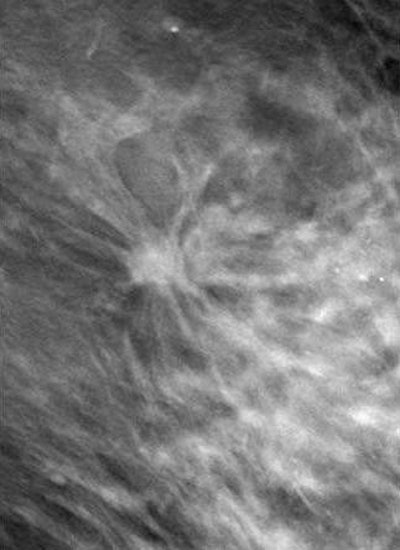

![]() |

| Left, mammogram shows very subtle architectural distortion (arrow). Right, magnification views shows mass, which is still very subtle (arrow). Images courtesy of Joseph Lo, Ph.D., Duke University Medical Center, Durham, NC, and Siemens Medical Solutions. |